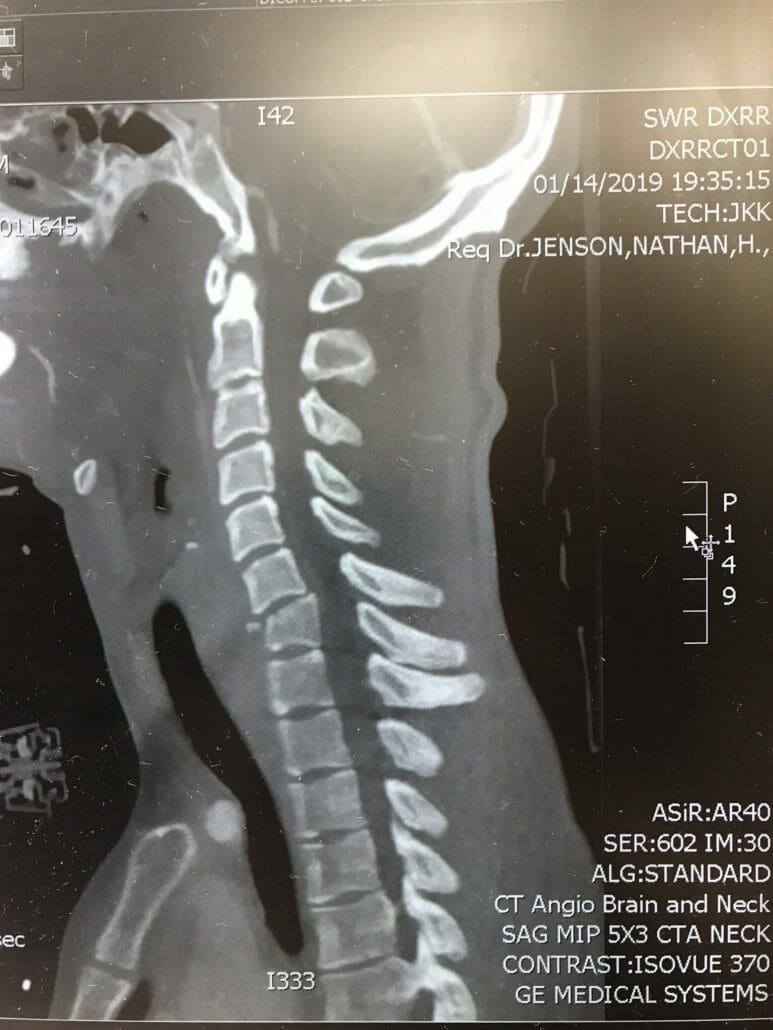

The break is in the area of vertebra C6 and 7. From the chest down he can not move at the moment. The paraplegia is caused by swelling and trauma in the area of the spinal canal. If the swelling goes back, the feeling in the limbs could come back. Whether he can fully recover from the accident is still open.